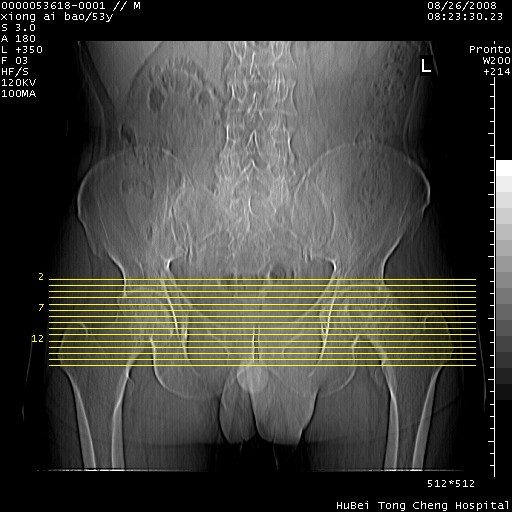

标题: CT15583:M,53Y。请老师指教分析骨盆及其他病变。 [打印本页]

标题: CT15583:M,53Y。请老师指教分析骨盆及其他病变。

股骨头坏死/腹股沟疝。

双侧股骨头无菌坏死,左侧腹股沟斜疝。

非常典型病例,双侧股骨头坏死伴双髋关节周围软组织肿胀,左腹股沟疝。

双侧股骨头坏死伴双髋关节周围软组织肿胀,左腹股沟疝。